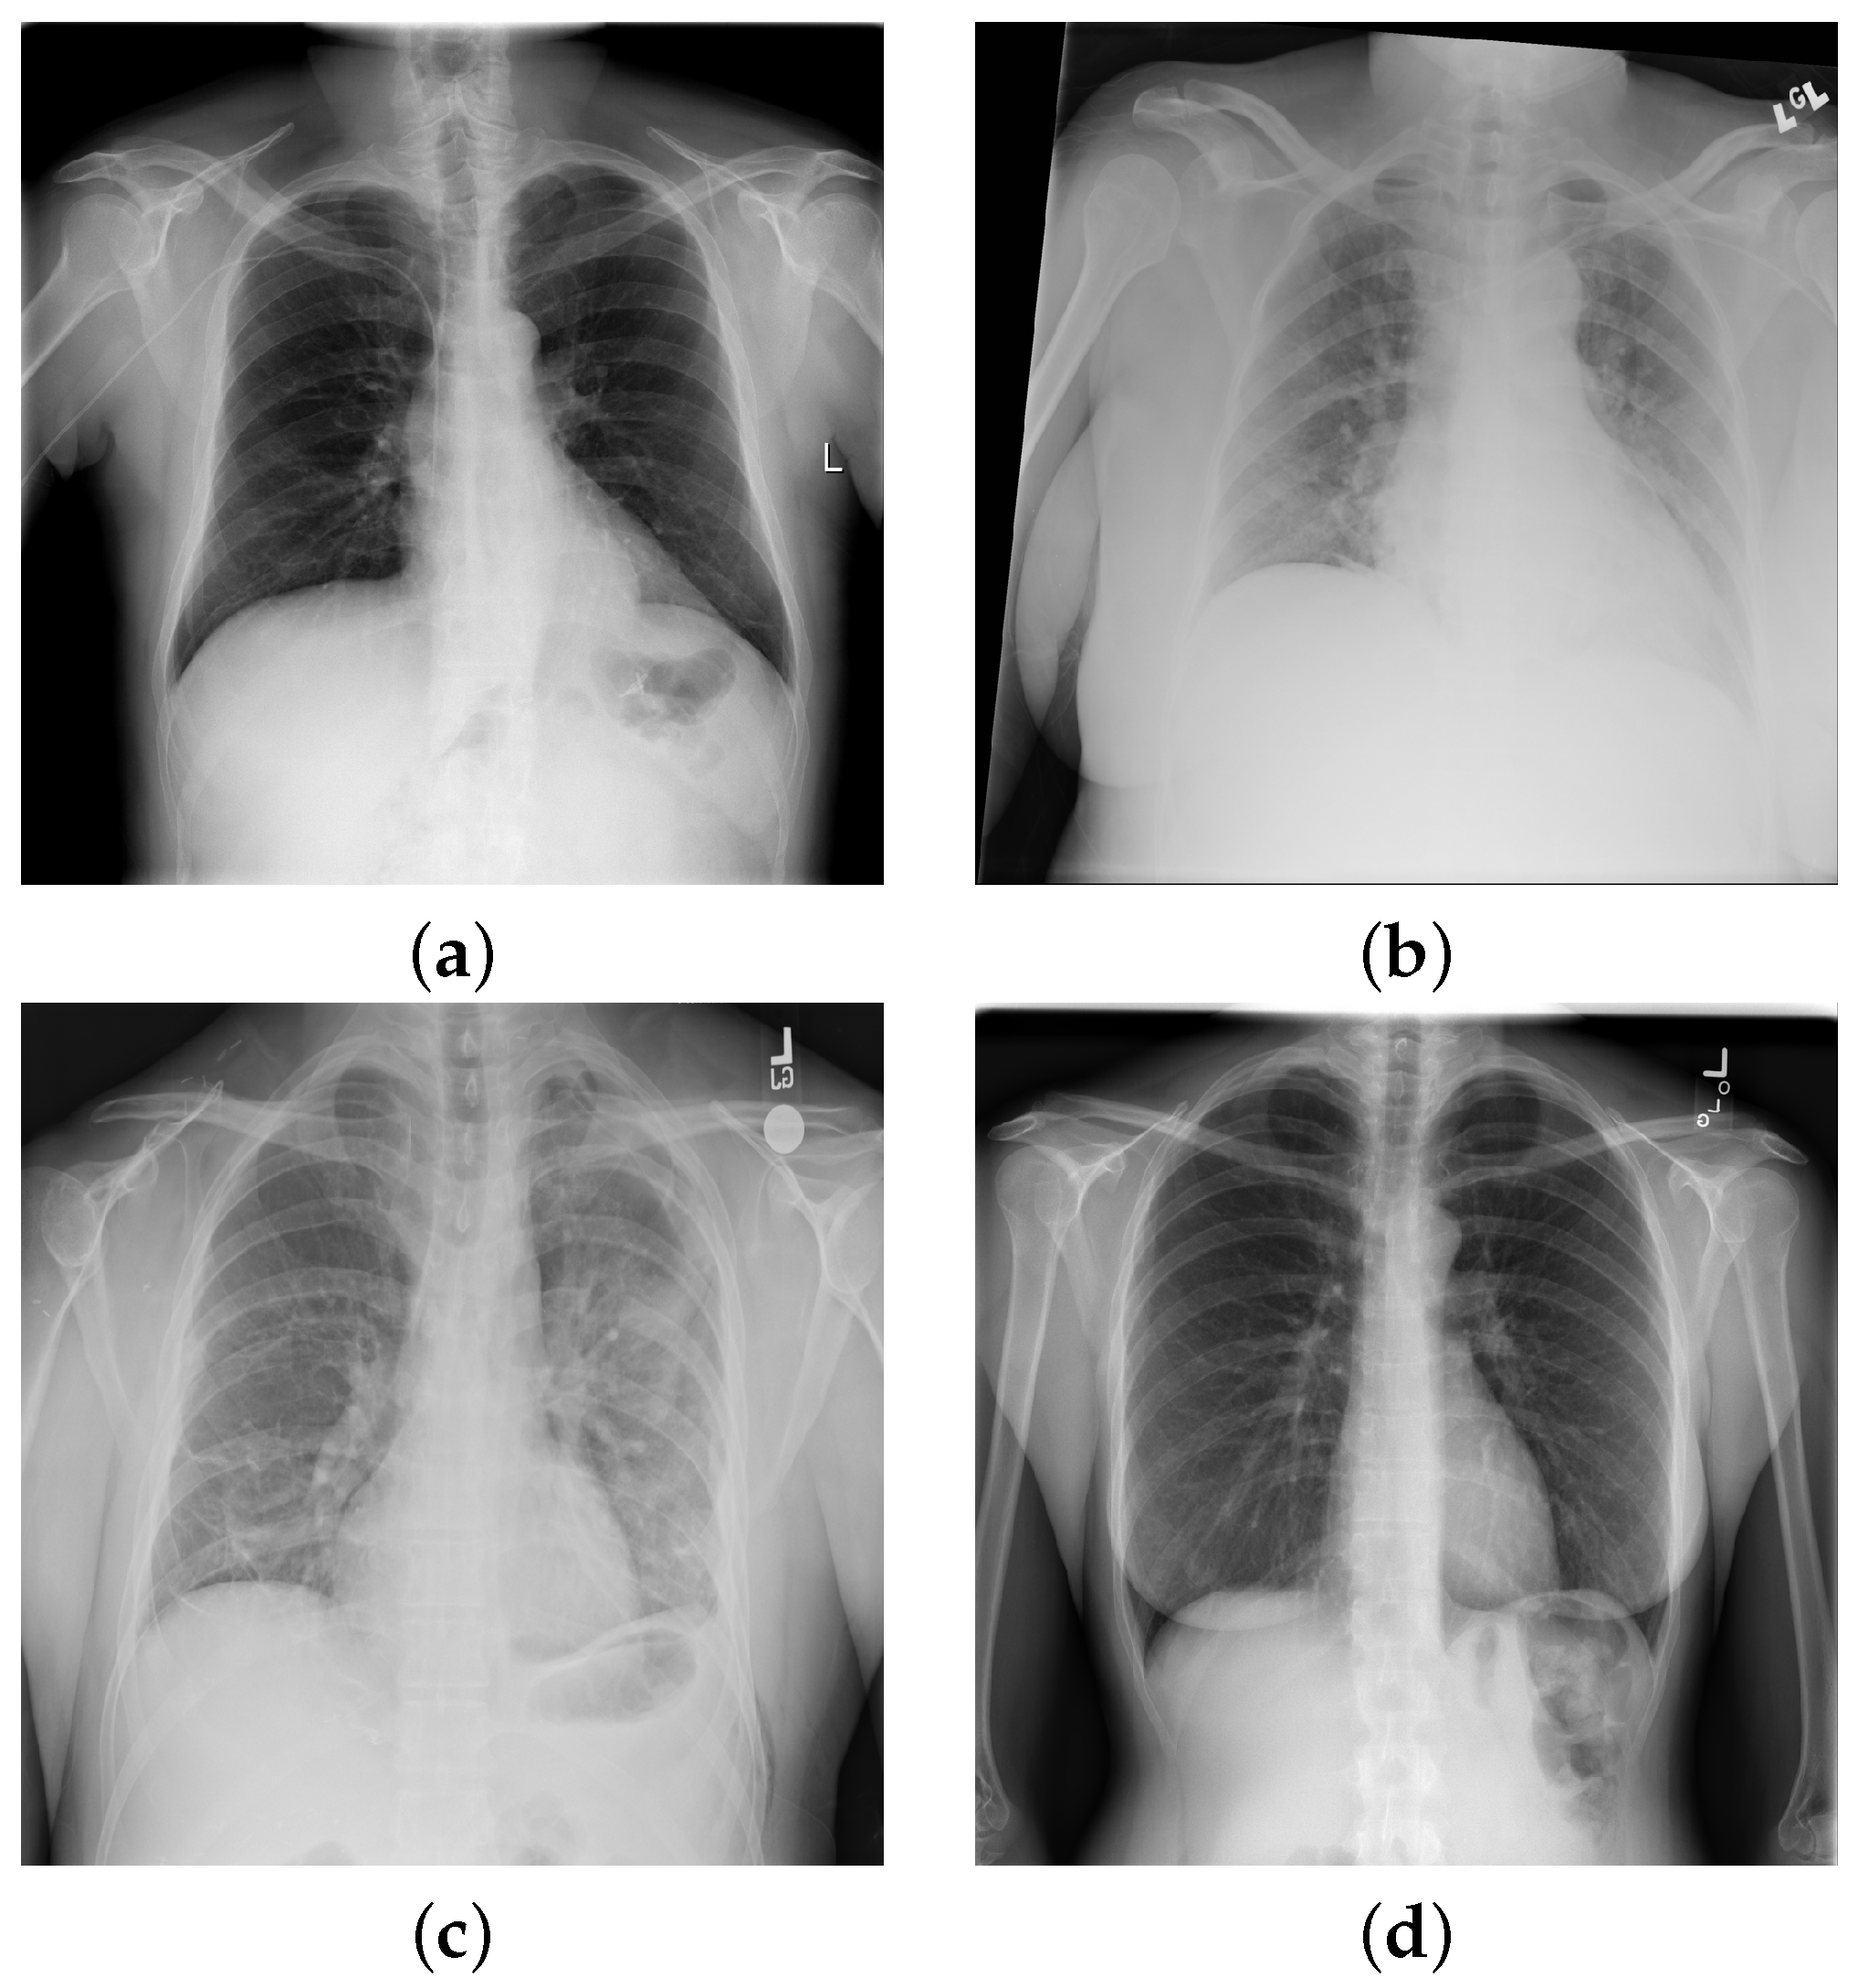

Pulmonary infiltrate is a non-specific term for any accumulated abnormal substance in the lungs; further differentiation is needed for pneumonia, atelectasis, hemorrhage, edema, fibrosis, etc. In Figure 2, we show selected X-rays for preview. Air spaces may be filled with fluid, pus, or cells, causing increased whiteness due to increased attenuation of the X-rays, called consolidation. The accumulation of fluid in the lungs in pulmonary edema has multiple signs, including pleural effusion, air space opacification in a batwing distribution, and enlargement of the heart (cardiomegaly).

The expansion of the lungs may be incomplete for various reasons. Atelectasis is the incomplete expansion of some regions of the pulmonary tissue, while pneumothorax (PTX) is complete lung collapse due to air entering the plural places. On plain radiographs, PTX can be identified by the visible visceral pleural edge, which appears as a thin sharp white line with no lung markings peripheral to this line, and we can detect nodules and masses that are abnormal growths in the lung, which may represent tumors. Malignant conditions may have other signs, such as thickening of the pleura. Inflammatory conditions, e.g., pneumonia, have distinctive signs as well, including patchy or large areas of consolidation.

Figure 2. Chest X-ray images with findings: (a) hernia; (b) atelectasis, cardiomegaly, edema, effusion, and infiltration; (c) cardiomegaly, consolidation, effusion emphysema, infiltration, pleural thickening, and pneumothorax; (d) no findings.